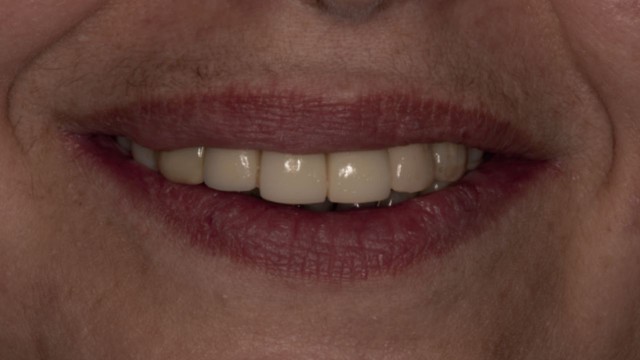

Sorriso della paziente con le protesi provvisorie. E’ stato possibile un ottimo recupero estetico e funzionale grazie anche all’aumento della dimensione verticale che ha riportato ad una corretta relazione tra le due arcate.